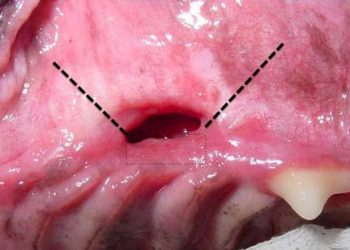

Yara Kanalı, fistül teriminin türkçe adı. Sore passage